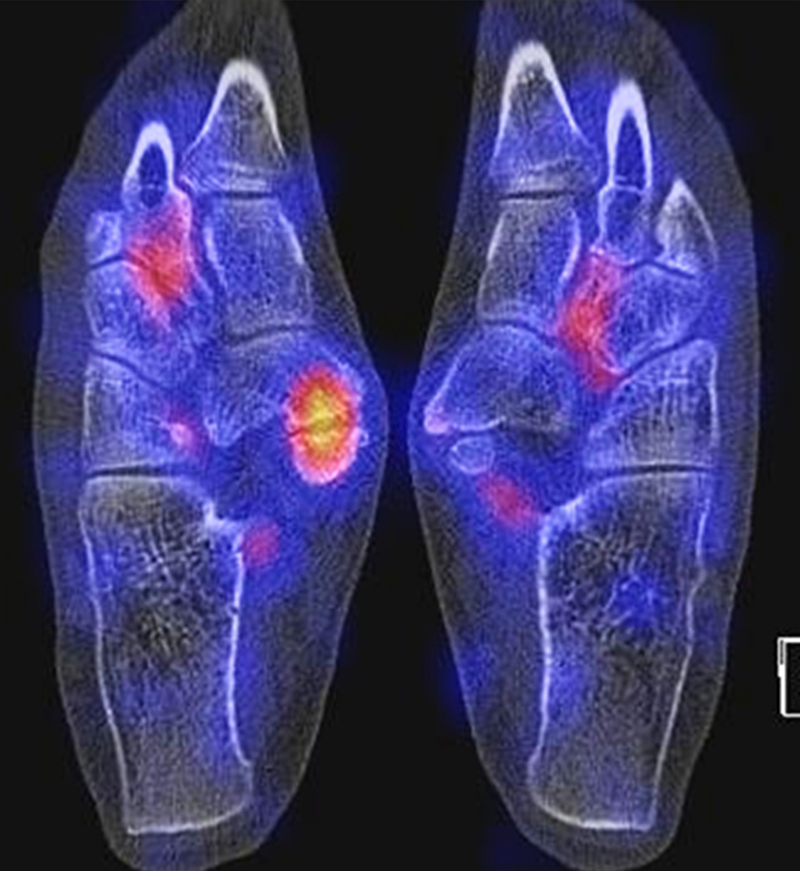

Bildbeispiele Arthrose für Arthrosen sind in den Abbildungen 1.1. bis 1.4. dargestellt:

Abbildung 1.1. zeigt eine isolierte aktivierte fortgeschrittene Arthrose des 3. Lisfranc-Gelenkes am linken Fuß. Klinisch bestanden belastungsabhängige Schmerzen plantar im Mittel-/Vorfuß.

Abbildung 1.2. zeigt eine ausgedehnte posttraumatische Arthrose im linken OSG. Der metabolische Focus liegt in der Hauptbelastungszone.